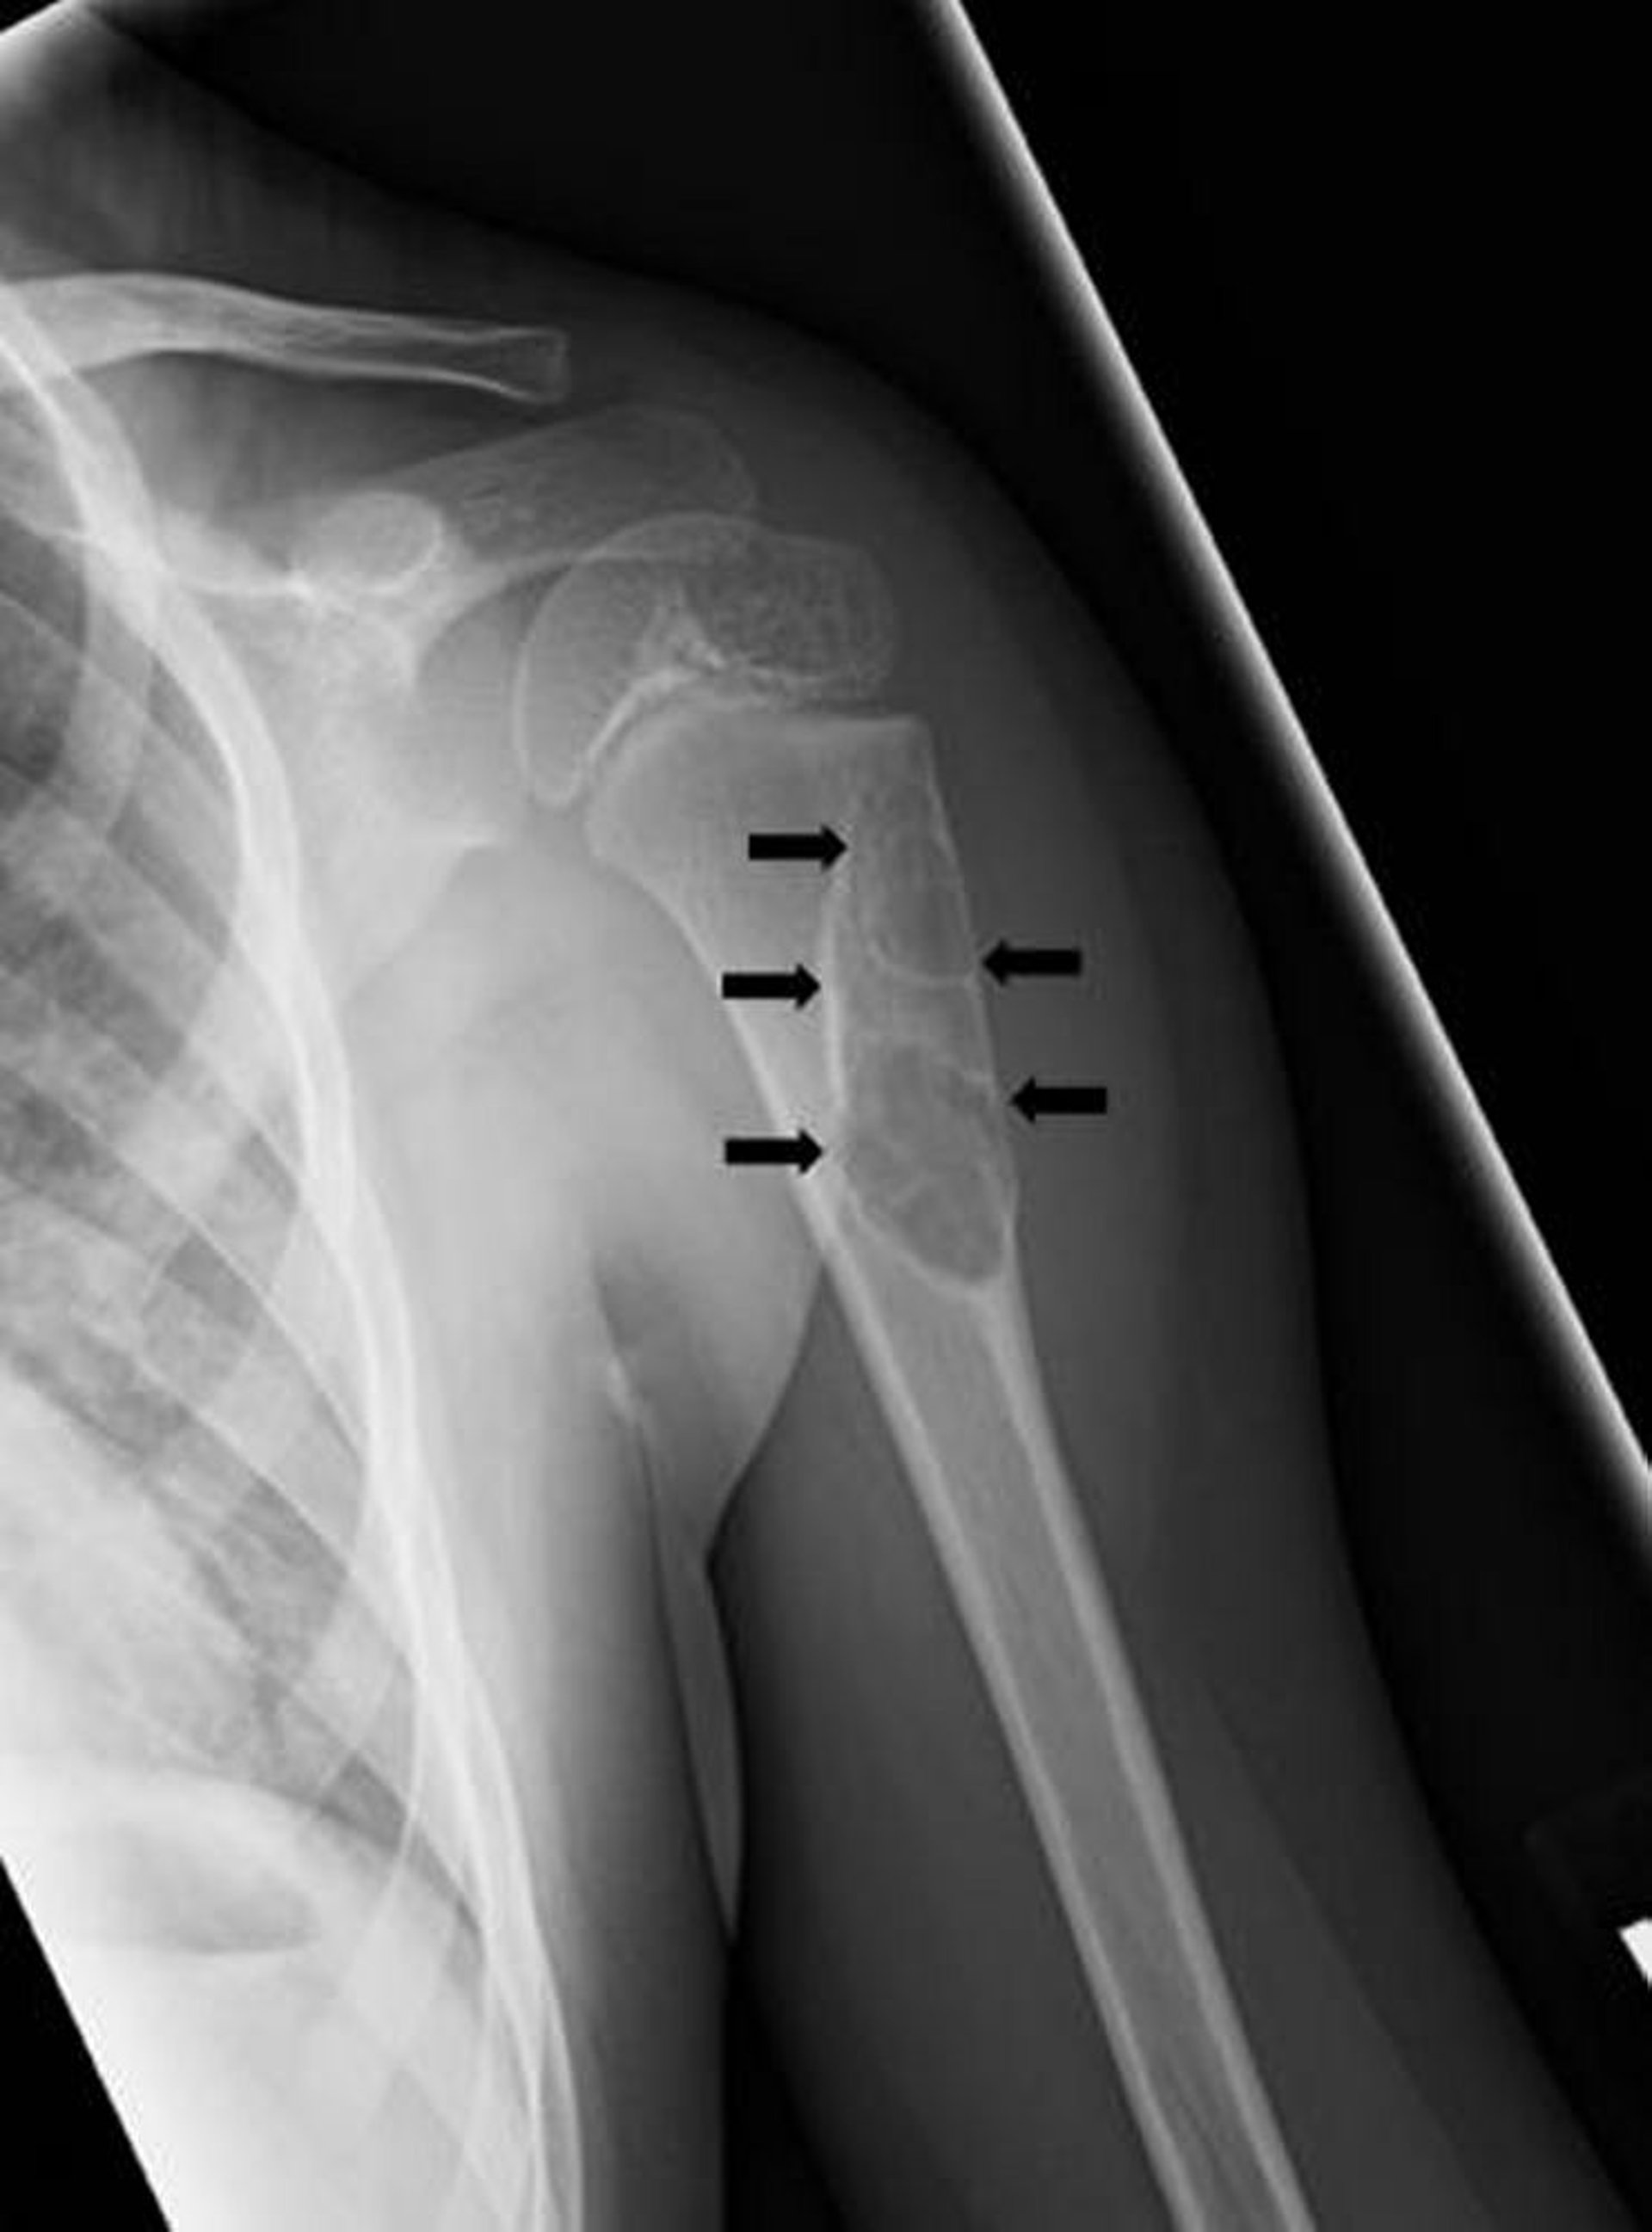

यह एक्स-रे ऊपरी बाँह की हड्डी में एक साधारण यूनिकैमेरल हड्डी के सिस्ट (तीर) को दिखाता है।